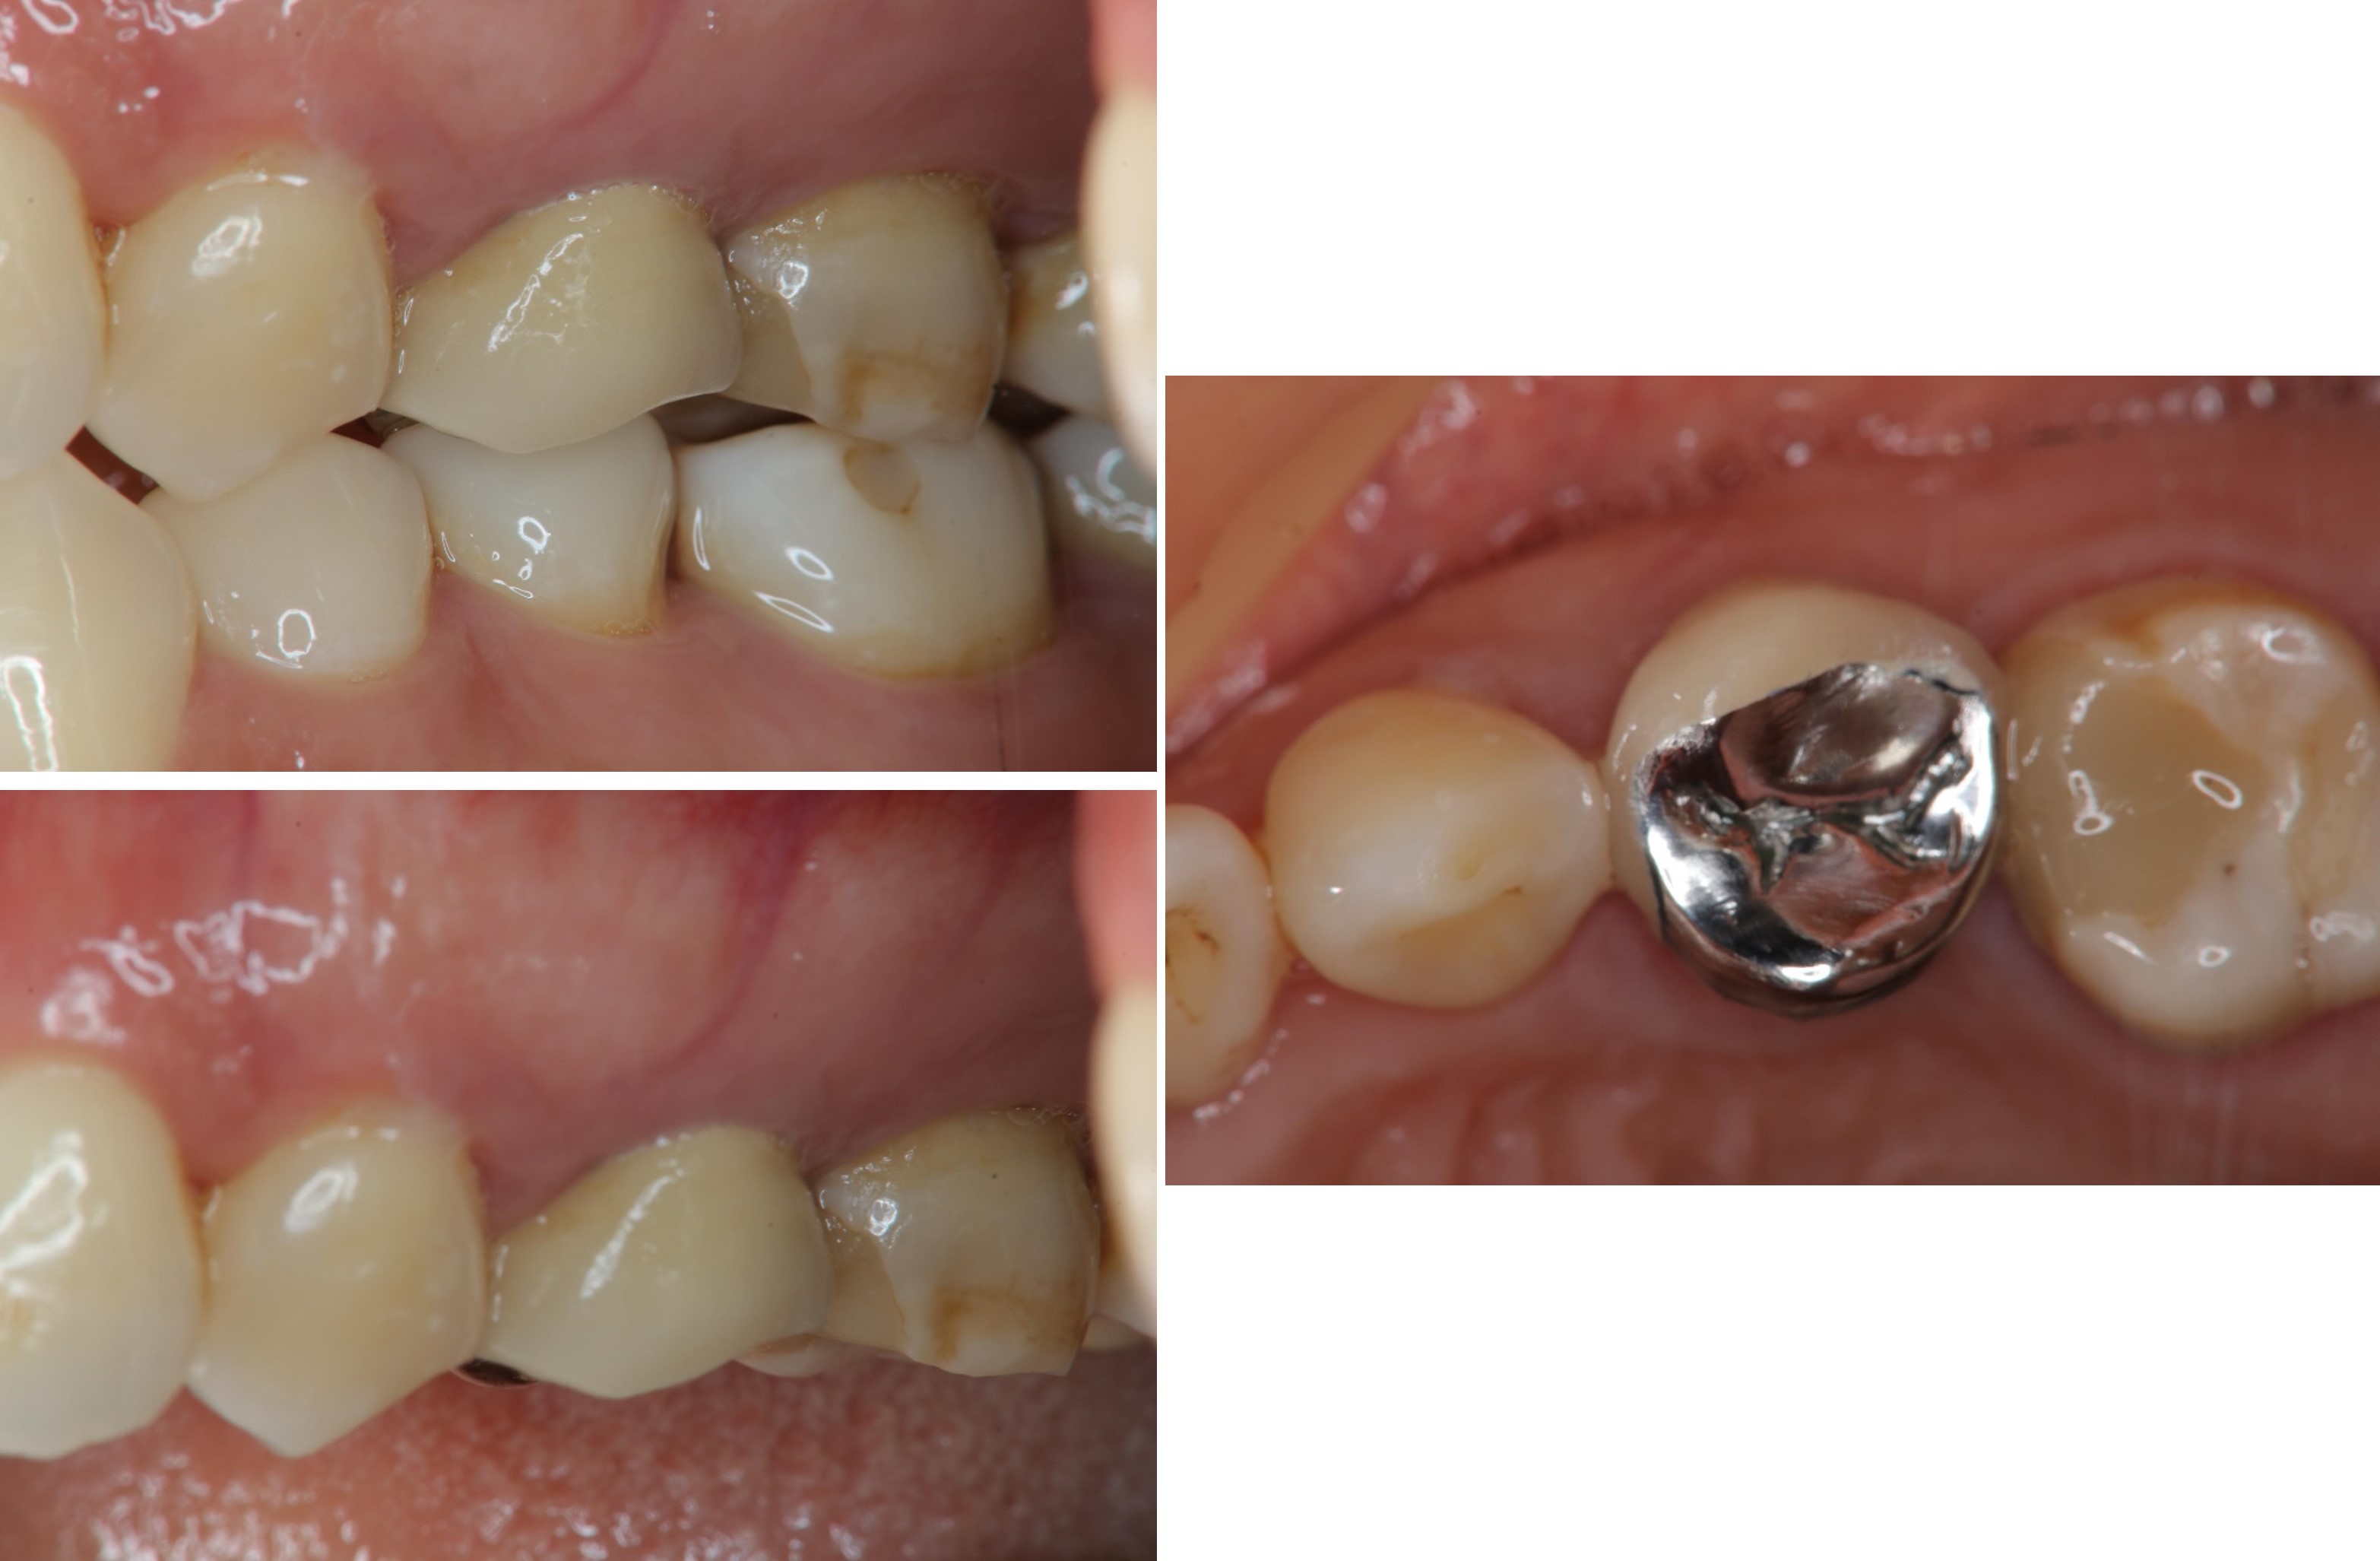

治療後,咬合良好

治療後,密合度良好

術前、術後比較